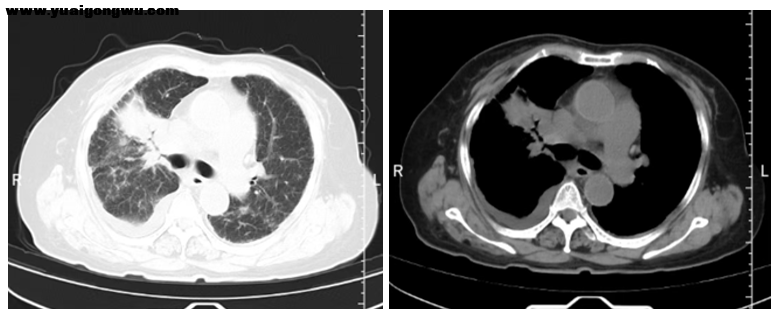

+ w! Y5 F2 [. a7 \6 u) t: q. @患者连线 感谢各位专家的建议。患者停用免疫药,是因使用两个周期后引发风湿性疾病,相关指标至今未下降,遵当地医生建议停药。患者基因检测结果为阴性,胃泌素释放肽前体肿瘤标志物自第二次化疗后至今均正常。第六次化疗后,患者因无法进行免疫维持治疗,改为口服依托泊苷;一个月后复查,原发灶肿瘤增大,此前第六次化疗后肿瘤曾明确失活,本次复查报告提示不除外炎性病变及病变可能。 ^4 H0 B* @5 G) k1 a( V

治疗效果如下: 2026-2-4复查胸腹CT,对比2025-12-11片: 1、左下肺外基底段病灶较前稍增大,请结合临床; 2、左侧胸膜局部增厚较前相似;支气管疾患并肺气肿,双肺少许慢性炎症同前;双肺间质性纤维化大致同前; 3、左锁骨上窝、纵隔及左肺门、脊柱前增大淋巴结较前增大增多,考虑转移性淋巴结; 4、左第2前肋及右第6肋腋段陈旧性骨折,不除外病理性骨折;胸椎骨转移瘤基本同前; 5、肝S6段新增转移瘤可能,余肝内转移瘤基本同前,建议MRI增强扫描; 6、双肺多发小结节,部分较前新增,不除外转移瘤,建议复查;余况同前,建议全身PET-CT检查。 - U+ A Y9 E1 ?

李成海教授(影像科) 梳理患者全部影像资料如下:2025年7月份初始胸部CT提示,左下叶有两个病灶,伴左胸膜增厚,左锁骨上、左肺门淋巴结转移,同时存在骨转移及肝脏多发转移。经治疗后,肝脏转移灶治疗效果显著,逐渐减少,后续多个治疗周期后,肝脏转移灶基本消失。2026年1月12日头部增强核磁显示,大脑脑膜、颅内出现转移灶及强化结节;1月24日复查CT对比2025年12月11日结果,左下叶外基底段病灶稍增大,胸膜增厚与既往一致,同时出现淋巴结增大及双肺新增小结节。结合影像表现,相较于治疗最佳时期,当前病灶增大、双肺新增小结节,转移概率较高。因目前不清楚新增结节具体大小,建议进一步行CT等检查完善评估。